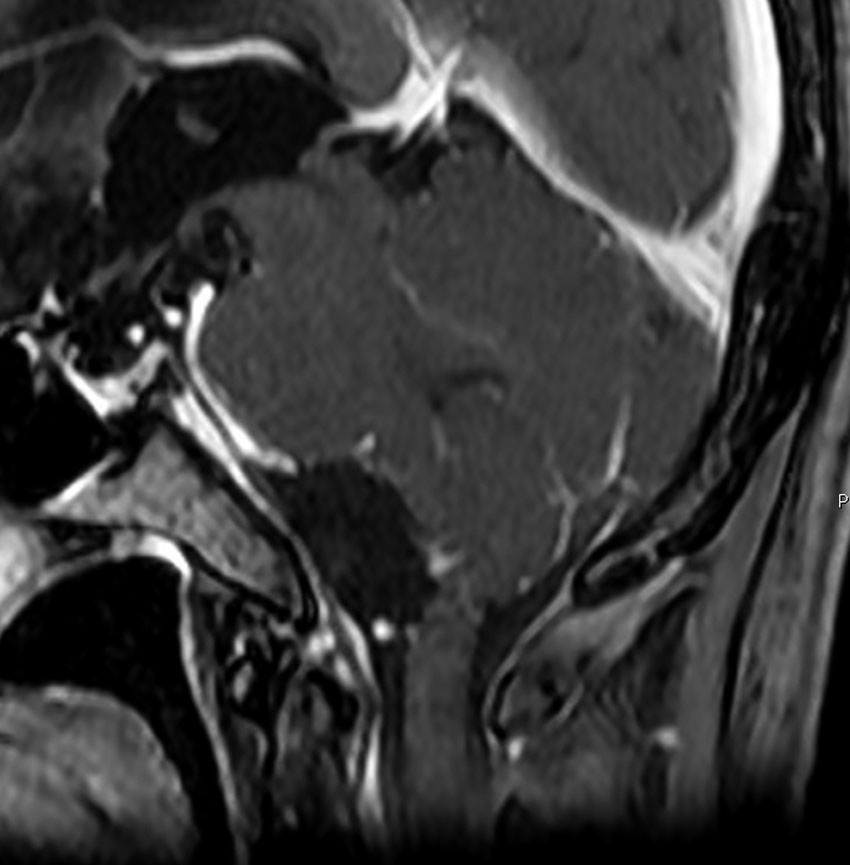

若い女性に偶然発見されたものです。直静脈洞と静脈洞交会の接合部あたりに発生したもので,静脈洞はほぼ閉塞に近い所見でした。しかし,この部分の静脈洞は,テント硬静脈側副路が発達することがあるので,硬膜を含めた積極的な摘出をすることは絶対にできません。もしほんの少しでも流れがある直静脈洞を閉塞させると短時間に脳死になるような脳静脈圧亢進が生じる可能性があるからです。静脈洞内に少し取り残して(右下の矢印)手術を終了しました。手術後には定位放射線治療を行って再増大を防ぎます,